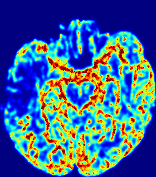

LesionRefer to captionRefer to captionRefer to captionRefer to captionRefer to captionRefer to caption𝐕rgbsubscript𝐕𝑟𝑔𝑏{\bf{V}}_{rgb}Refer to captionRefer to captionRefer to captionRefer to captionRefer to captionRefer to caption𝐕2subscriptnorm𝐕2{\|\bf{V}}\|_{2}Refer to captionRefer to captionRefer to captionRefer to captionRefer to captionRefer to captionRefer to caption3.53.53.52.82.82.82.12.12.11.41.41.40.70.70.70.00.00.0(mm/s)𝑚𝑚𝑠(mm/s)D𝐷DRefer to captionRefer to captionRefer to captionRefer to captionRefer to captionRefer to captionRefer to caption0.0200.0200.0200.0160.0160.0160.0120.0120.0120.0080.0080.0080.0040.0040.0040.0000.0000.000(mm2/s)𝑚superscript𝑚2𝑠(mm^{2}/s)Slice #1Slice #2Slice #3Slice #4Slice #5Slice #6

Figure 3: PIANO feature maps for one stroke patient, where the lesion is located in the left hemisphere. Top row: segmented stroke lesion region (white) on different slices, obtained from ISLES 2017. The corresponding slices for the PIANO feature maps are shown in the following rows.

For a better insight into an estimated velocity field 𝐕𝐕{\bf{V}} and diffusion field 𝐃𝐃{\bf{D}}, we compute the following maps: (1) 𝐕rgbsubscript𝐕𝑟𝑔𝑏{\bf{V}}_{rgb}: Color-coded orientation map of 𝐕=(Vx,Vy,Vz)T𝐕superscriptsuperscript𝑉𝑥superscript𝑉𝑦superscript𝑉𝑧𝑇{\bf{V}}=(V^{x},V^{y},V^{z})^{T}, obtained by normalizing 𝐕𝐕{\bf{V}} to unit length and mapping its 3 components to red, green, blue respectively; (2) 𝐕2subscriptnorm𝐕2\|{\bf{V}}\|_{2}: 222 norm of 𝐕𝐕{\bf{V}}; (3) D𝐷D: scalar field in Eq. 5.

Fig. 3 and Fig. 4 show the PIANO feature maps estimated from two ISLES 2017 patients: all are highly consistent with the lesion in both cases. Details of the blood flow trajectories are revealed in 𝐕rgbsubscript𝐕𝑟𝑔𝑏{\bf{V}}_{rgb} by the ridged patterns and the sharp changes of colors in the unaffected (right) hemisphere, while the flat patterns appearing within the lesion provide little directional information about the velocity and indicate low velocity magnitudes. Velocity magnitudes are more directly visualized via 𝐕2subscriptnorm𝐕2\|{\bf{V}}\|_{2}, from which one can easily locate the lesion where 𝐕2subscriptnorm𝐕2\|{\bf{V}}\|_{2} is low. D𝐷D also indicates lower diffusion values in the lesion, though with less contrast potentially due to the fact that it captures the accumulated effect of CA diffusion at the voxel-level.